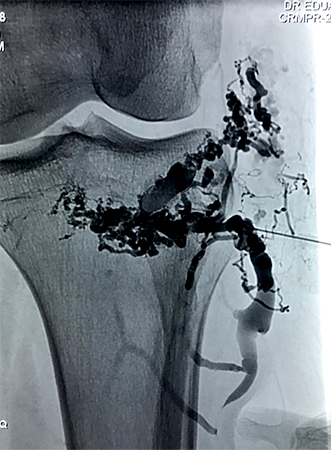

Embolizações de Malformações Vasculares

Existem vários tipos diferentes de malformações vasculares congênitas. A maioria de nós já teve a oportunidade de observar bebês com os hemangiomas superficiais, que embora causem certo espanto, geralmente regridem espontaneamente até os sete anos de idade. Todavia, há malformações que seguem crescendo durante toda a vida, podendo causar prejuízo estético e funcional ao paciente. Atualmente, é possível através de técnicas de cateterização superseletiva ou mesmo punção direta, injetar substâncias que provocarão a oclusão dessas lesões, levando à sua regressão ou até completo desaparecimento.